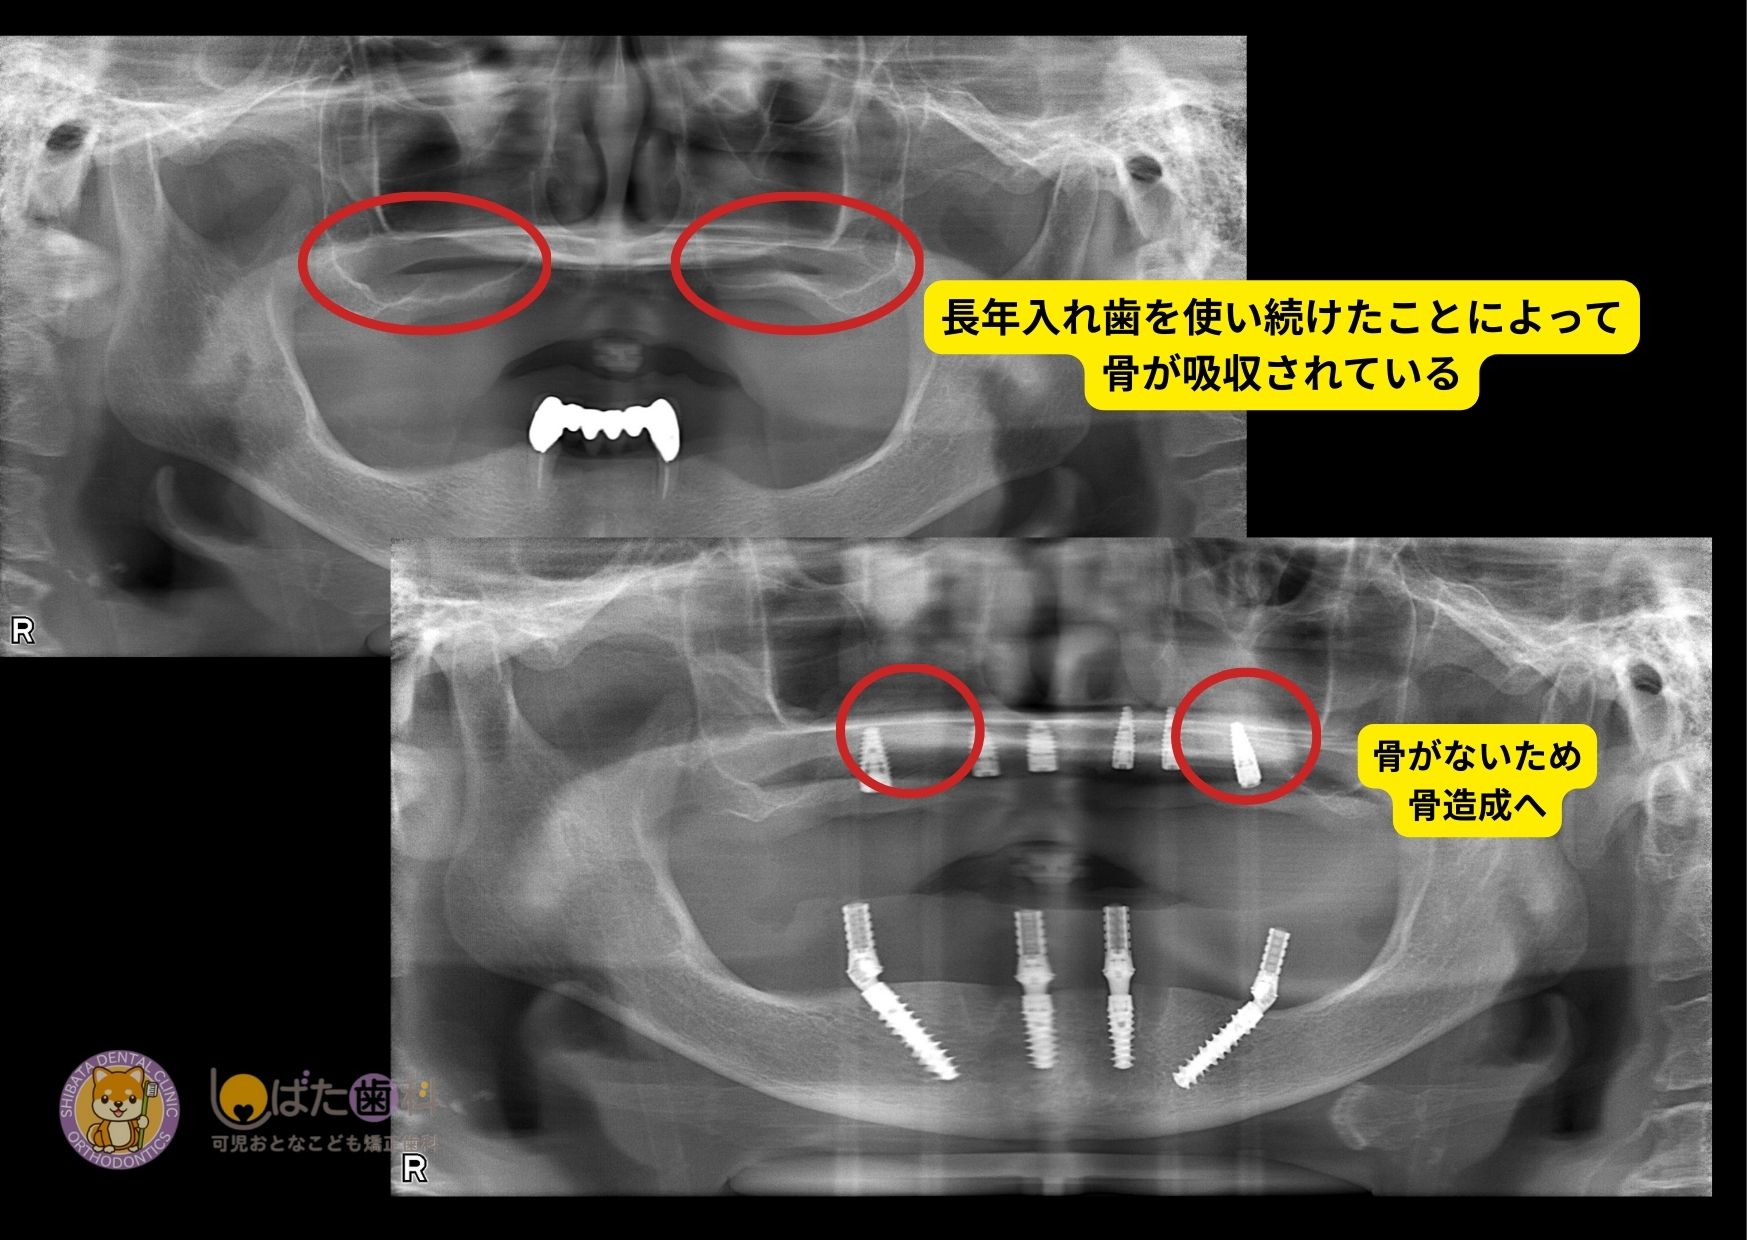

精密検査を行い、CT検査をしたところ、長年の歯の欠損と入れ歯の使用により骨吸収は進んでいましたが診断の結果。オールオン4治療をできる状態でした。

まさに「今なら選択できる」そんなタイミングでした。